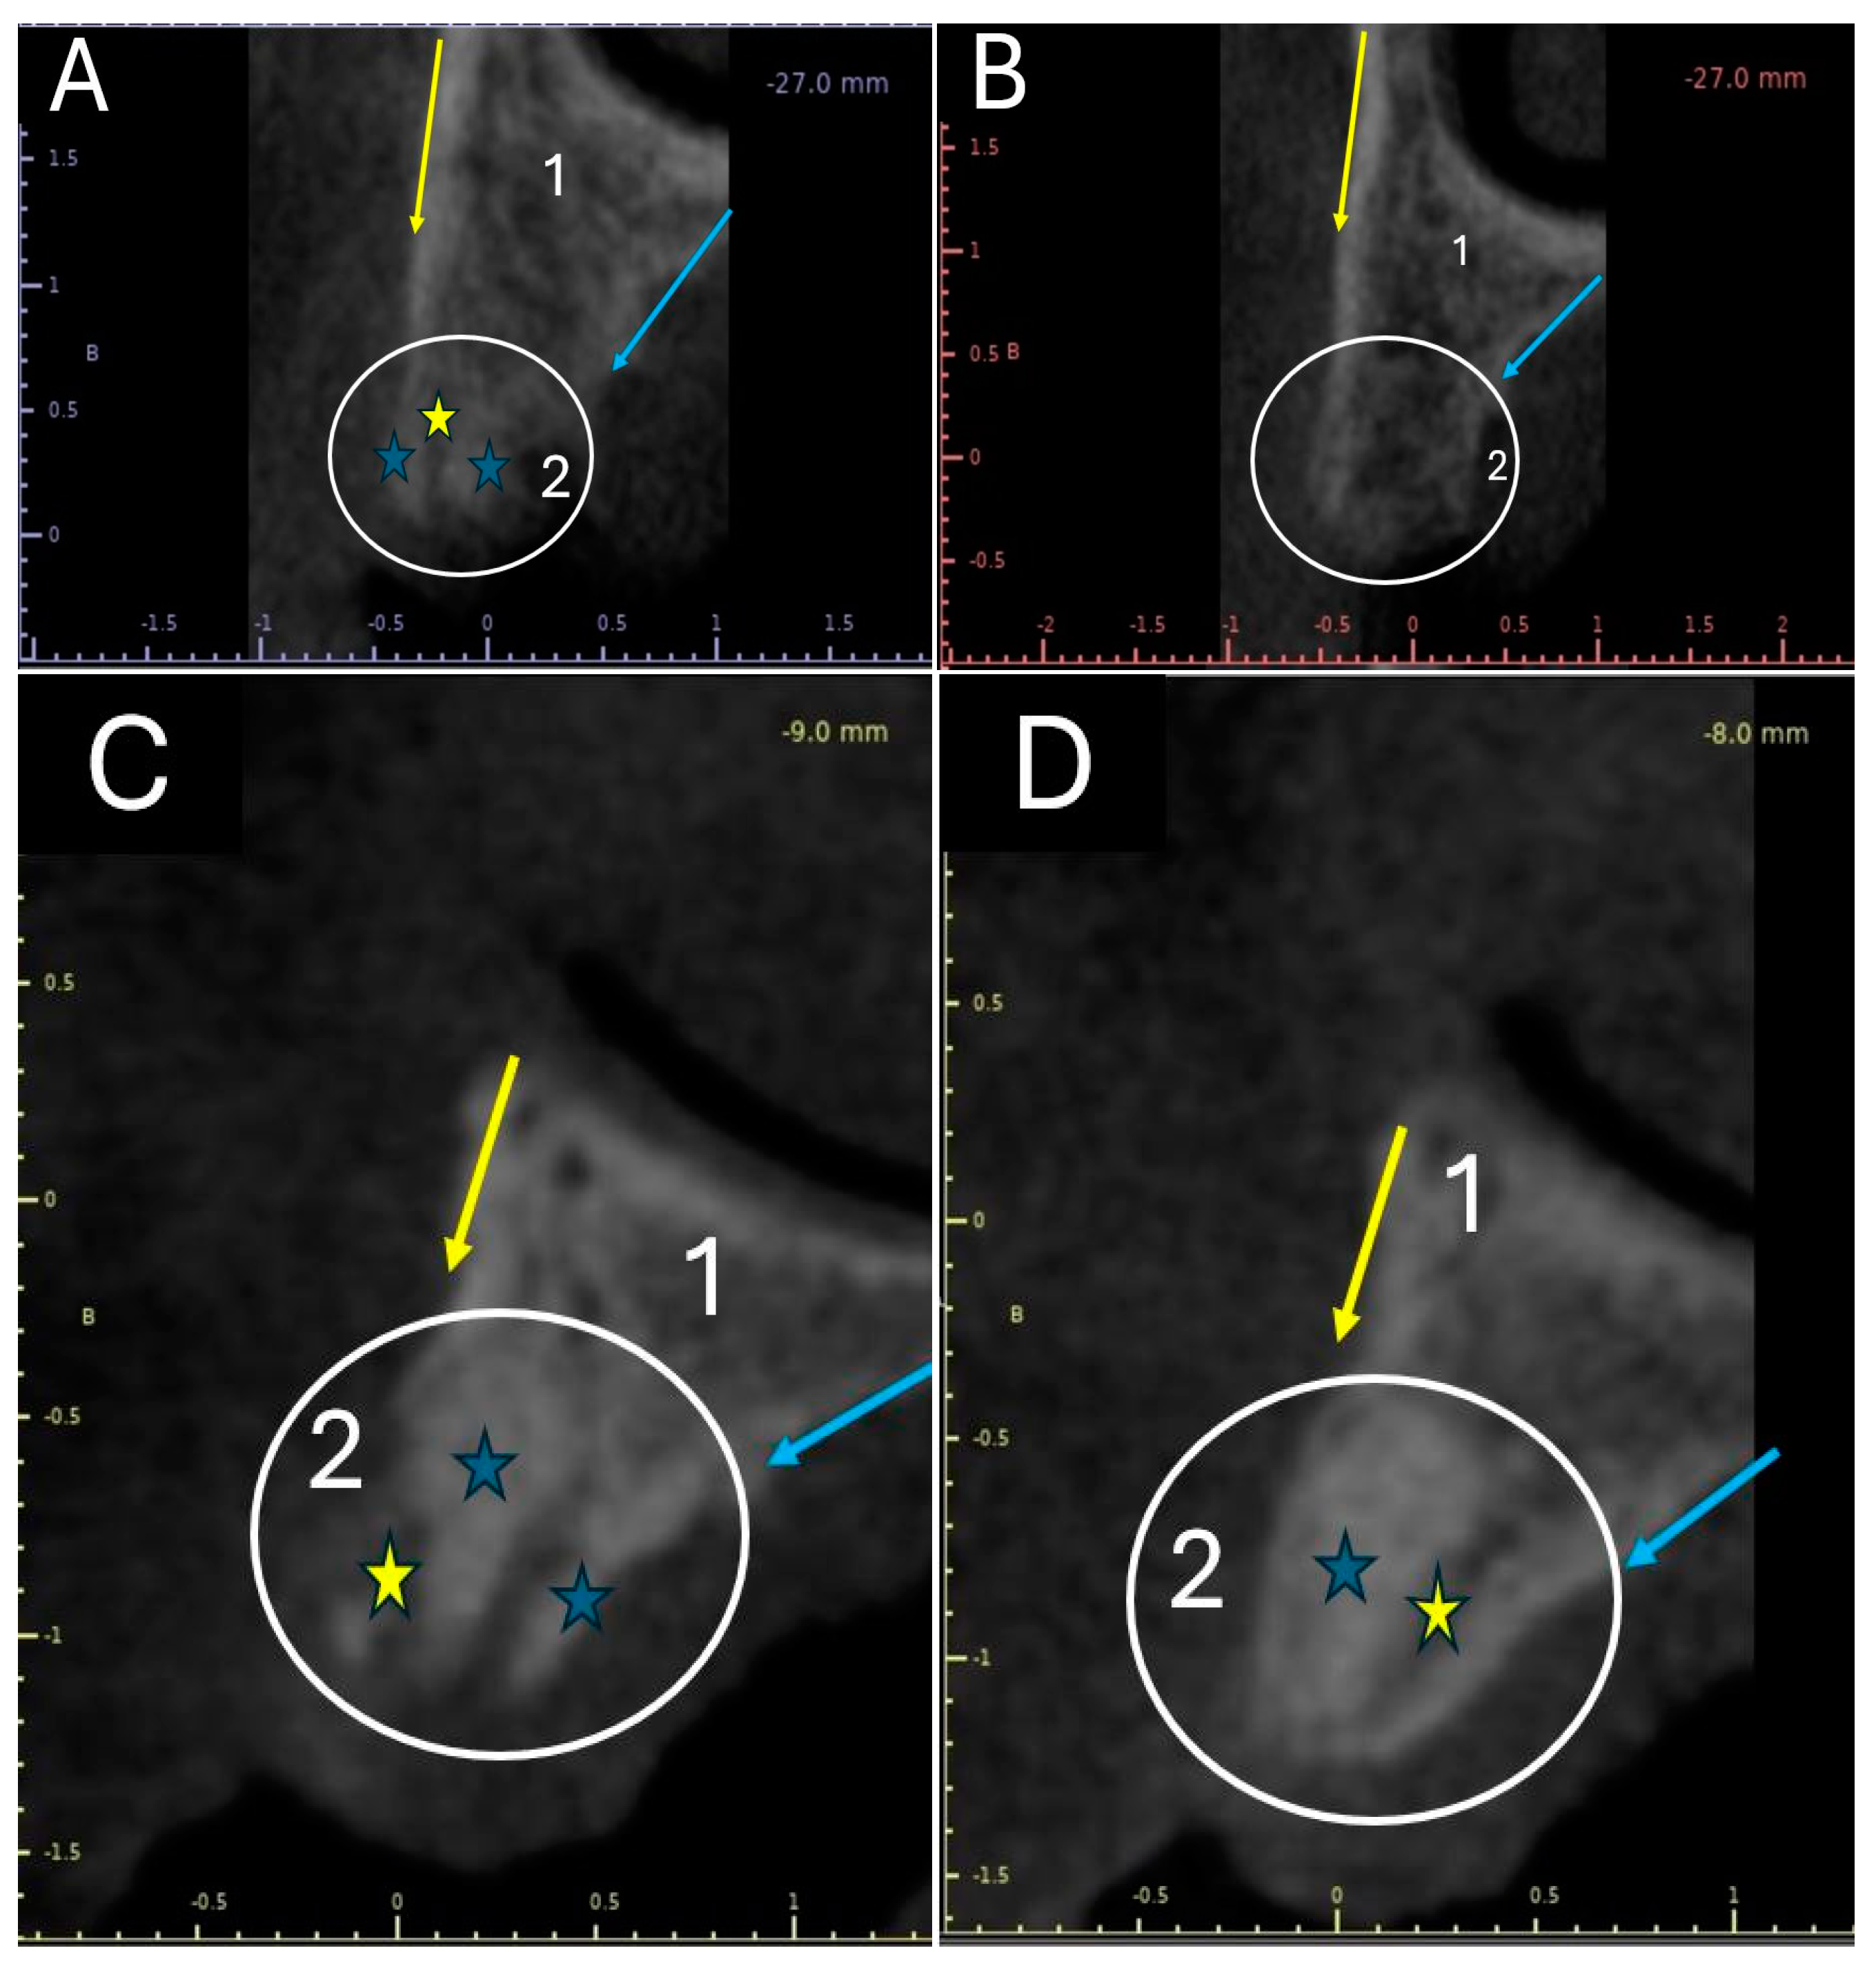

Once the grafts were placed, tomographic studies of the grafted alveoli were performed. Figure 2 shows the tomographic images of an alveolus grafted with apatite and another grafted with apatite–collagen, obtained 30 and 180 days post-graft.

Figure 2A shows the image of an alveolus one month after being grafted with apatite–collagen. The circle indicates the area that was preserved with the xenograft. When comparing the part of the alveolus that contains native bone, identified with the number 1, with the part of the alveolus that contains the grafted tissue, identified with the number 2, an area of more radiopaque appearance (blue stars) and a radiolucent area (yellow star) are observed in the grafted area. However, at 6 months, the grafted area (white circle in Figure 2B) presents the radiographic appearance typical of a cancellous bone, with radiopaque and radiolucent areas being very similar to what is observed in the portion of the socket that contains the remaining bone.

Figure 2C shows an apatite-grafted alveolus one month later. The white circle corresponds to the grafted area. Very dense radiopaque areas (blue stars) and some radiolucent areas (yellow stars) can be seen. When comparing sectors 1 and 2, it is observed that the grafted area (identified with the number 2) has more radiopaque or dense areas than the native bone area, identified with the number 1. Figure 2D shows the same socket at 6 months of grafting. The persistence of a very dense radiopaque zone occupying most of the grafted area (blue star in the white circle) is observed, with a radiolucent zone identified with a yellow star. When comparing the area with remnant bone (identified with the number 1) with the grafted area (identified with the number 2), it is observed that zone 1 has a radiographic appearance typical of a cancellous bone. In contrast, zone No. 2 has a very radiopaque appearance.

The radiographic findings in the tomographic images shown in Figure 2 indicate that the alveolus grafted with apatite material presents a slower replacement process than the alveolus grafted with the apatite–collagen material. This suggests that the two materials’ creeping substitution process differs, occurring more quickly with apatite–collagen. This is evidenced in Figure 2B, where, after 6 months, the material appears to have been replaced by spongy-type bone tissue.

Figure 2. Tomographic images of grafted alveoli in cross-sections. Yellow arrow: The vestibular surface of the ridge. Blue arrow: The palatal surface of the flange. 1: Area of the alveolus made up of remnant or native bone. 2: Area of the socket where the graft was placed. Blue stars: Radiopaque appearance zone. Yellow star: Area of radiolucent appearance. White circle: Grafted area of the alveolus. (A) Alveolus grafted with apatite–collagen at 1 month. (B) Alveolus grafted with apatite–collagen at 1 month. (C) Alveolus grafted with apatite at 1 month. (D) Alveolus grafted with apatite at 6 months.